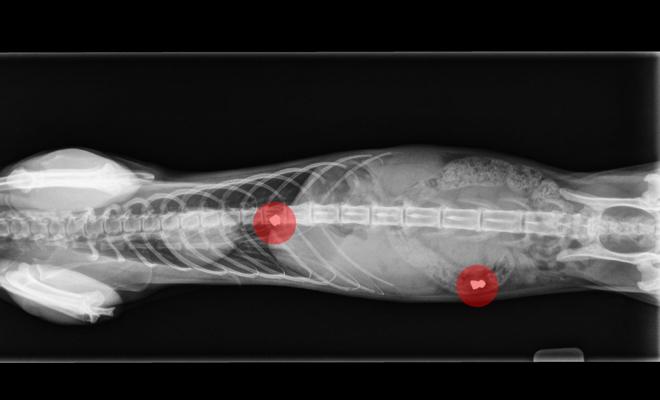

Dos de los felinos fueron recogidos por una protectora y operados en una clínica con sendos balines alojados en la columna vertebral

Los primeros gatos malheridos por perdigonazos procedentes de una colonia controlada de la urbanización Aldeamayor Golf llegaron hace un año a una clínica veterinaria y la escena, con otros dos felinos lesionados por sendos disparos a bocajarro que «les dejaron paralíticos», se repitió los pasados días 8 de agosto y 27 de septiembre.

«Es evidente que son disparos realizados de manera alevosa para hacer daño a unos animales que, pese a ser callejeros, cuentan con todos los cuidados tanto por parte de un vecino como de una protectora (Ronroneos al rescate) que se encarga de vacunarlos y esterilizarlos», explica el veterinario Daniel de Celis, de la clínica Fierecillas, donde fueron atendidas las últimas víctimas.